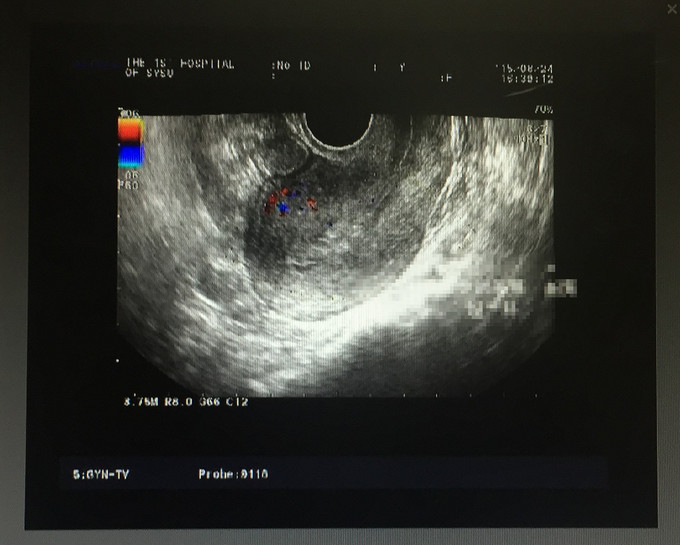

妇检:外阴:发育正常,阴毛分布正常;阴道:通畅,未见异常分泌物,粘膜正常无充血,水肿,无血污;宫颈:光滑,常大,无接触性出血,无抬举痛,未见活动性出血。宫体:前位,常大,无压痛。双附件:未扪及包块,无触痛。 外院输卵管造影:子宫形态,大小正常,右输卵管积液,左侧输卵管间质部梗阻。 我院B超:子宫内膜不均,考虑子宫内膜多发息肉。